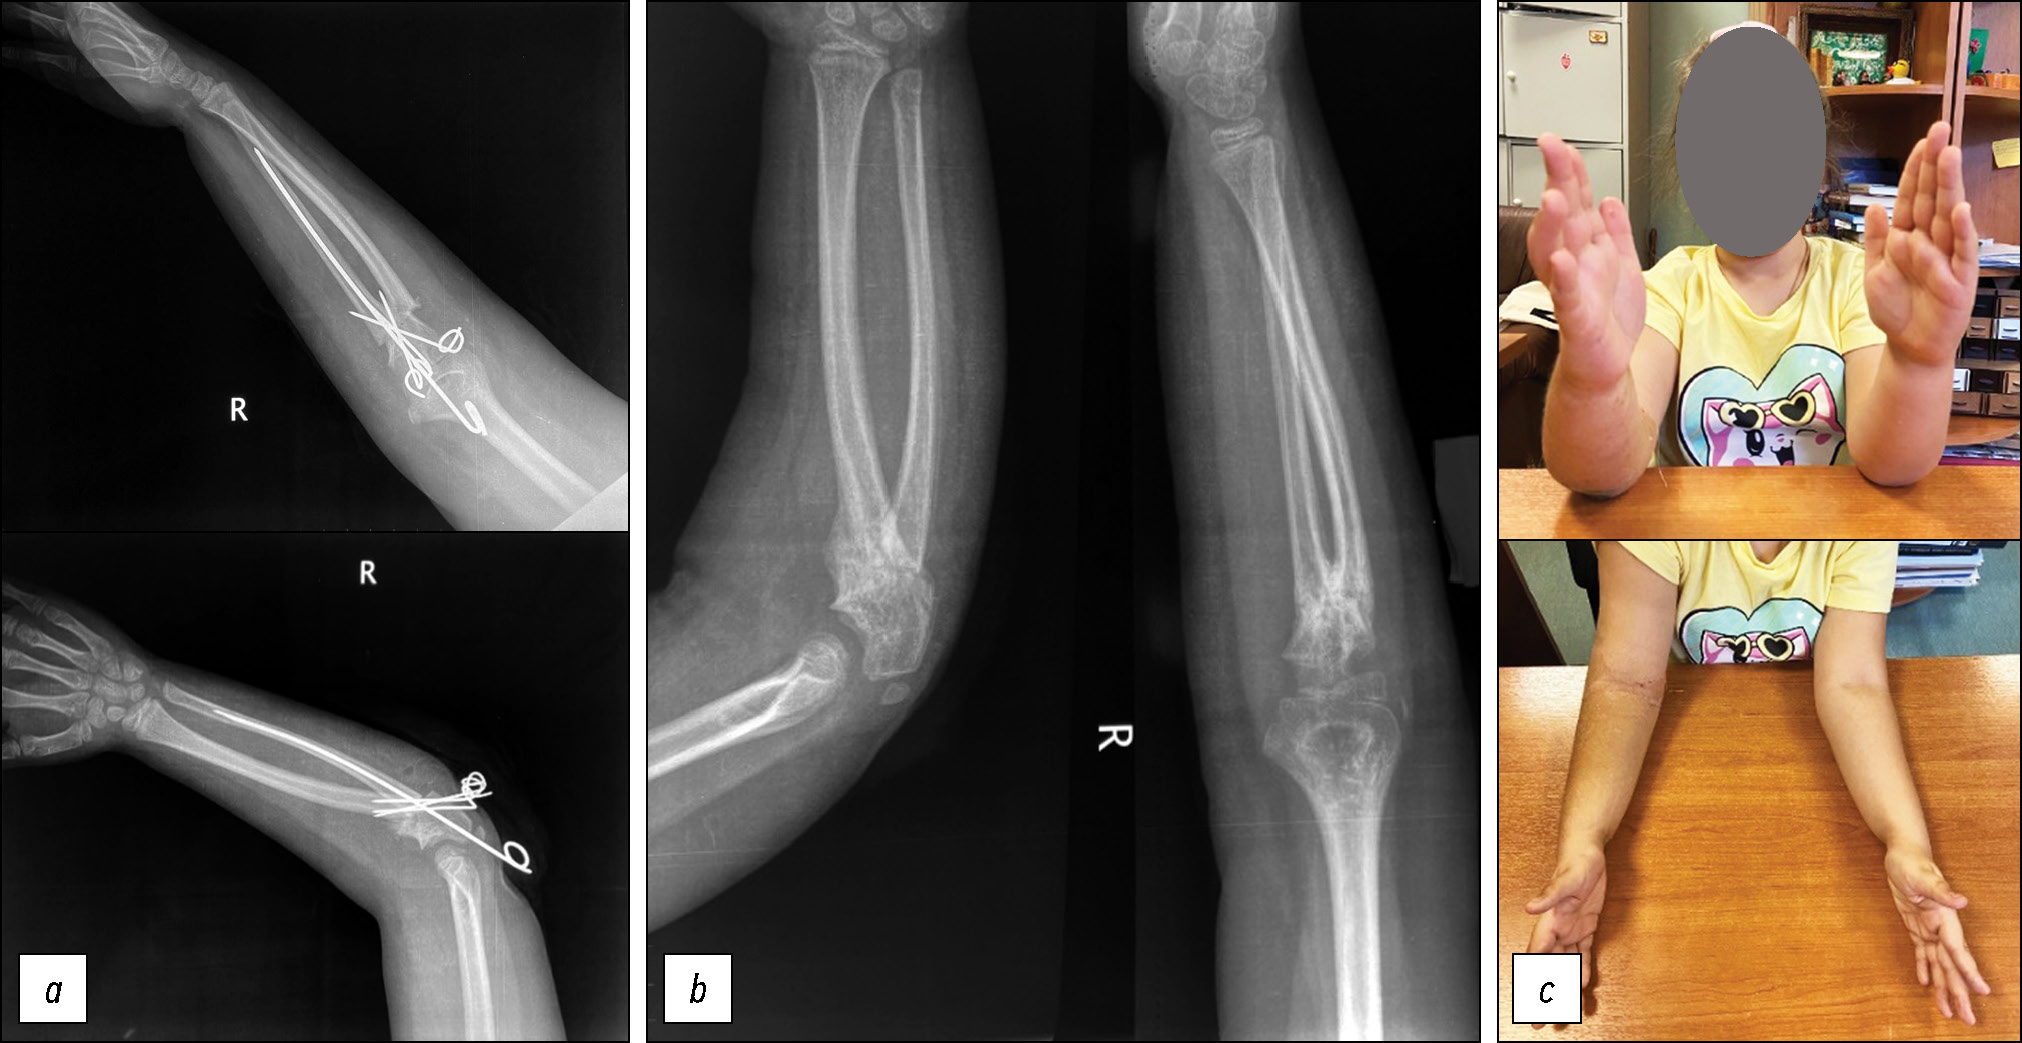

Проведена операция: корригирующая остеотомия костей правого предплечья на уровне синостоза, металло-остеосинтез спицами (рис. 4, a). Наложена гипсовая лонгета по задней поверхности плеча и предплечья от пястно-фаланговых суставов до средней трети плеча в положении сгибания локтевого сустава под 90 градусов с выведением предплечья в среднее положение. Послеоперационный период протекал без осложнений, активные движения правой кистью пациентка начала выполнять сразу после окончания действия проводниковой анестезии. Спицы удалены через 8 недель по достижении сращения зоны остеотомии (рис. 4, b, с). На контрольных консультациях мать ребёнка отметила улучшение самообслуживания девочки, облегчение процессов письма и рисования правой рукой. Через полгода пациентка поступила в отделение для оперативного лечения на левой руке. Выполнена аналогичная операция с фиксацией спицами и наложением гипсовой лонгеты. В послеоперационном периоде невропатии глубокой ветви лучевого нерва не наблюдалось. Спицы удалены через 8 недель по достижении консолидации костных отломков.

Рис. 4. Результаты послеоперационного осмотра пациентки Ч.: а — правая верхняя конечность после оперативного лечения (июль 2023 г.); b — правая верхняя конечность после удаления спиц — консолидация зоны остеотомии; с — сравнение клинически оперированной правой и неоперированной левой верхней конечности (дата согласия на публикацию от законного представителя — 01.07.2023 г.).

Fig. 4. Postoperative examination findings of patient Ch.: a, right upper limb after surgery (July 2023); b, right upper limb after wire removal, consolidation of the osteotomy site; c, clinical comparison of the operated right and non-operated left upper limbs (date of legal representative’s consent for publication: July 1, 2023).